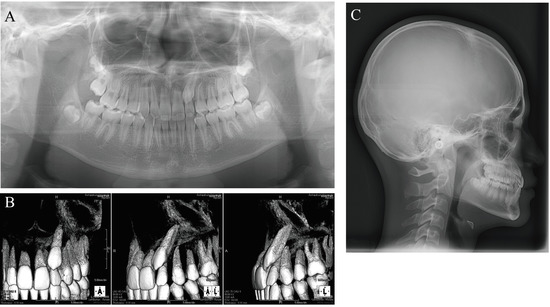

Figure 3. Initial radiographs. (A) Panoramic radiograph. (B) Cone-beam computed tomography. (C) Lateral cephalogram (age, 14 years 4 months).

Panoramic X-ray and cone-beam computed tomography (CBCT) images showed that the maxillary left canine had erupted ectopically due to eruption disturbance. The maxillary left canine was mesially inclined with its crown near the labial root surface of the lateral incisor. The cusp of the canine was positioned more mesially than the lateral incisor axis. There was no evidence of canine contact with the lateral incisor or root resorption of the adjacent permanent teeth. There was no abnormality in the number of teeth. Tooth germs of the maxillary and mandibular right and left third molars were observed; the tooth germ of the maxillary left third molar was almost as large as the ipsilateral first and second molars.

Lateral cephalometric radiography showed no discordance in the anteroposterior position of the maxilla and mandible, with SNA of 90.5°, SNB of 88.5°, and ANB of 2.0°. Vertically, the patient had a low Frankfort-mandibular plane angle (FMA) of 14.0°. U-1 to NA was 2.0 mm/14.0°, indicating that the axis of the maxillary central incisor was normal, but that it was lingually positioned. L-1 to NB was 2.0 mm/14.5° and the FMIA was 80.5°, indicating that the mandibular central incisor was inclined and positioned lingually. The resulting interincisal angle was 150.0°, a large value exceeding 2SD (Figure 3).